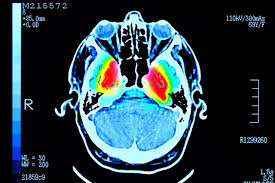

مغز انسان

کشف ۴ سن طلایی برای مغز

پژوهشگران دانشگاه کمبریج نشان داده‌اند که مغز تا اوایل دهه سوم زندگی در مرحله نوجوانی باقی می‌ماند، یعنی زمانی که ما به «اوج» می‌رسیم.

مغز به طور دائم در پاسخ به دانش و تجربه جدید در حال تغییر است. اما این تحقیق نشان می‌دهد که این فرآیند از تولد تا مرگ یک مسیر یکنواخت و هموار نیست.

این الگو‌ها تنها به لطف تعداد زیاد اسکن‌های مغزی که در این مطالعه در دسترس بوده‌اند، آشکار شده‌اند. این تحقیق در نشریه «نیچر کامینوکیشن» منتشر شده است.